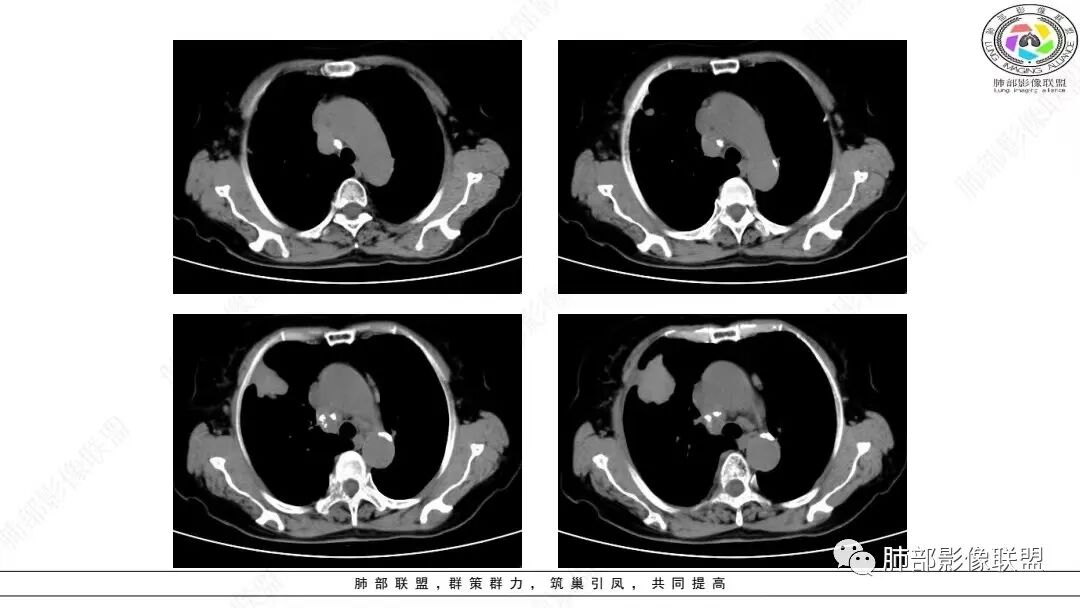

2.影像学特点:右肺上叶前段胸膜下不规则较大团块影,边界清楚欠光整,浅分叶,肺血管支气管出入,边缘膨隆胸膜凹陷具有一定张力,未见典型粗短毛刺,部分围以边界清楚的磨玻璃影,灶周小叶间隔增厚。块影密度不均,渐进性强化,可见砂砾样钙化,未见明显液化坏死或空洞。增强后病灶显示渐进性强化。MIP显示病灶内肺动脉穿行、并部分肺动脉受侵变细。纵隔及右锁骨上(胸廓入口)见肿大淋巴结。两肺可见多发大小不一的结节影,边界清楚,随机分布。

目前部分研究提示肺LELC大多以单发周围型肿块为主,多发生肺下叶,多数病灶可见分叶及毛刺征。Ma等口1发现,41例肺LELC患者中30例(73.17%)表现为较大的中央型肿块,以右肺中叶和左肺下叶多见,边界清楚,呈分叶状,常引起阻塞性肺炎。本组肺LELC中央型占54.10%,多发生于右肺中叶、两肺下叶,最大径平均(5.42±2.64)ClTI,肿块型多见(79.92%),边界较清,边缘常见分叶,且以浅分叶为主,可伴毛刺,超过半数(54.10%)伴有阻塞性肺炎或肺不张改变。

大多数学者认为肺LELC患者易发生纵隔和肺门淋巴结肿大。本组68.44%患者伴肺门和/或纵隔淋巴结肿大,65.57%发生淋巴结转移,且淋巴结最大短径为(2.04±0.90)crn,提示以CT淋巴结最大短径1 cm为标准大致区分肺LELC患者淋巴结是否转移具有较高敏感度。

本组大部分病灶(64.75%)CT平扫密度均匀;增强后多数病灶以中度(71.75%)、渐进性强化(75.13%)为主,动脉期病灶内常见异常细小杂乱血管影(55.96%)。    笔者据此认为密度均匀且不易出现坏死、呈中度渐进性延时强化为肺LELC的特点,可能与病灶内部含有丰富的淋巴细胞浸润和大量纤维组织增生及胶质有关;病灶内部分细小杂乱血管影可追踪为支气管动脉,推测可能为新生肿瘤血管,提示肿瘤血供丰富,不易出现坏死;但新生肿瘤血管通常不成熟,血管通透性增高,致使对比剂外渗,使肿瘤表现为延迟强化。肺LELC生长较快时,由于血供不足,也可出现液化坏死及钙化等改变。肺LELC密度均匀、液化坏死较少及延迟强化,可作为其与肺鳞癌或腺癌的鉴别要点。